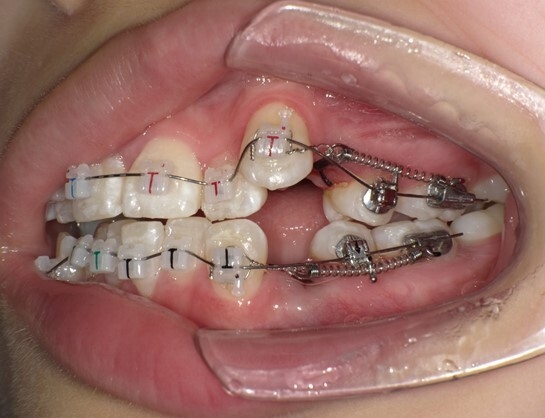

患者は13歳8か月の女子。主訴は左上に八重歯があること。上顎両側、下顎左側第一小臼歯を同時抜歯し、JET systemで治療を行ったところ動的治療期間は7か月であった。前歯部のトルクコントロール、上下顎正中の一致、咬合関係の改善が行われた。抜歯により誘発されたRAPを利用したJET systemでの治療は、治療期間の短縮に寄与し、患者QOLを向上させることが示唆された。